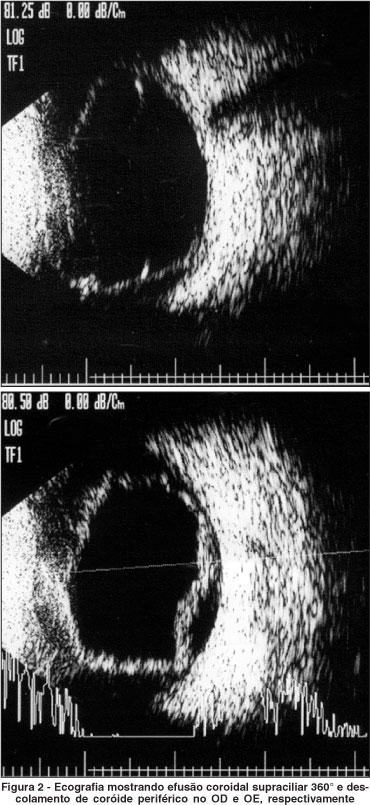

Nesse mesmo dia, foi realizada ecografia ocular que demonstrou efusão coroidal 360° com descolamento de coróide periférico em AO (Figura 2). As medidas da profundidade da câmara anterior, espessura cristaliniana e cavidade vítrea do OD eram 1,6 mm, 5,4 mm e 15,2 mm respectivamente e apresentavam-se similares no OE.

Sulfametoxazol e trimetoprima (cotrimoxazol) é uma combinação de drogas amplamente usada no tratamento e profilaxia de inúmeras infecções sistêmicas. Esta droga e outras derivadas da sulfa podem causar uma síndrome ocular rara caracterizada por efusão coroidal supracililar com miopização transitória e glaucoma por fechamento angular. A maioria dos autores atribui o glaucoma ao edema do corpo ciliar que leva ao deslocamento anterior do diafragma irido-cristaliniano causando fechamento do ângulo camerular. Este trabalho descreve um caso raro no qual a síndrome ocorreu após o uso desta combinação de drogas e evoluiu para um desfecho desfavorável. Paciente de 49 anos, sexo masculino, branco com diagnóstico de síndrome da imunodeficiência adquirida iniciou tratamento profilático para Pneumocystis carinii com cotrimoxazol. Quatro dias após, apresentou quadro de dor ocular, hiperemia e quemose conjuntival, glaucoma agudo por fechamento angular com pressões intra-oculares maiores que 50 mmHg e efusão coroidal 360º, com os achados presentes nos dois olhos. Nesse mesmo dia, a medicação foi suspensa com diminuição da pressão intra-ocular após quatro dias. O paciente evoluiu com catarata total e phthisis bulbi bilateral nos dois meses subseqüentes. Os casos já descritos mencionam a melhora clínica completa do quadro ocular após a suspensão da medicação. Este seria o primeiro caso na literatura no qual a evolução foi desfavorável apesar do diagnóstico e da suspensão precoce da medicação causadora.